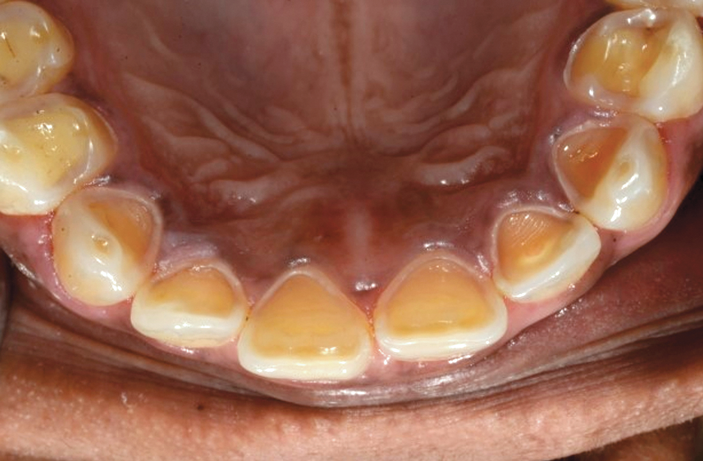

Gastroesophageal reflux (GER) disease (GERD), silent GERD, and other anorexic conditions produce loss of hard tissue on lingual surfaces due to acidic or protease challenges over time. GER applies to conditions when an incidental ocassion of reflux action occurs, such as drinking too much alcohol, or an event of undiagiosed food allergy. It is of interest that Fauchaud in the 1700s did not appreciate the differences between the chemical effects of biocorrosion and the effects of friction, which is a physical mechanism.28,46 He was attempting as a physician to explain oral or systemic conditions using terms available at that time. Chronicity is a key factor separating a pathologic state from more normal health. Figure 3 illustrates a patient with anorexia nervosa, which is an example of chronic endogenous biocorrosion.

Fig 3. A clinical example of severe chronic endogenous biocorrosion effects from anorexia nervosa. This patient was diagnosed and treated by a physician for this condition, which left lingual maxillary enamel almost free of this hard tissue. (Photograph is courtesy of Ali Tunkiwala, MDS, used with his permission.)